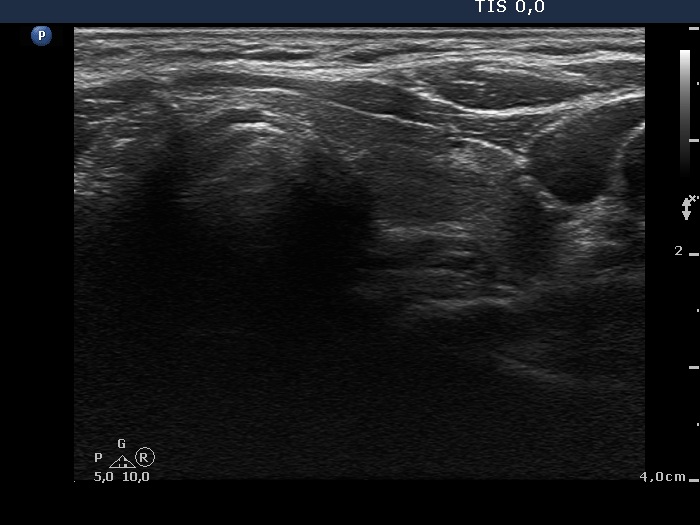

Ultrasonography: the right thyroid was echonormal while the left lobe contained moderately hypoechogenic areas with a 50% echogenicity index. There was a hypoechogenic mass lower and lateral to the right thyroid. The lesion did not present a regular hilum.